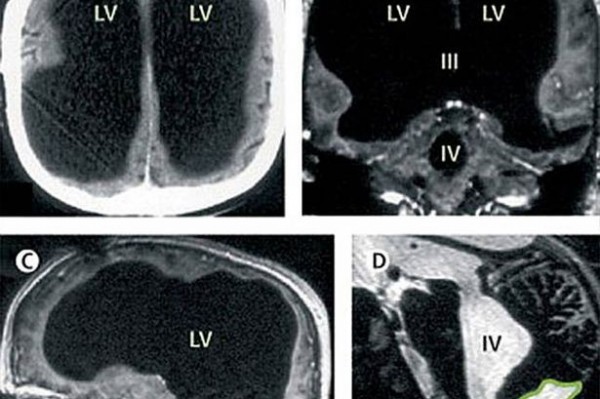

法國男子檢查時被發現,自己只有「半個」腦袋。(取自鏡報)

根據《鏡報》報導,這一位不願具名的法國男子,因腳傷而入院治療,在檢查過程中醫生赫然發現,他只剩半邊腦袋,然而令人驚訝的是,他的生活幾乎沒有受到影響,唯一問題是智力稍低於正常。

據悉,該名男子年幼時曾經罹患腦積水,醫生當時以分流管排走積水,直到14歲時移走。但他的腦部之後仍然有積水的問題,隨著症狀加劇,腦物質也逐漸被分解,到最後他喪失了50%至75%的腦物質。醫生於2007年發現問題後,再為男子排走腦內積水。

研究該例特殊個案的科學家弗耶(Lionel Feuillet)指出,該名男子左右腦皆有縮小,而這些區域原先負責的功能,如動作、語言、聽覺和視覺等,在經過8年的研究後,科學家相信該男子的腦能夠自行重組,由其他仍在的部分負責喪失部分原先所負責的工作。科學家表示,此個案同時證實,智力和腦部大小並沒有一定的關係。

從X光照中可以看出,該男子的腦內部份有明顯縮小。(取自鏡報)